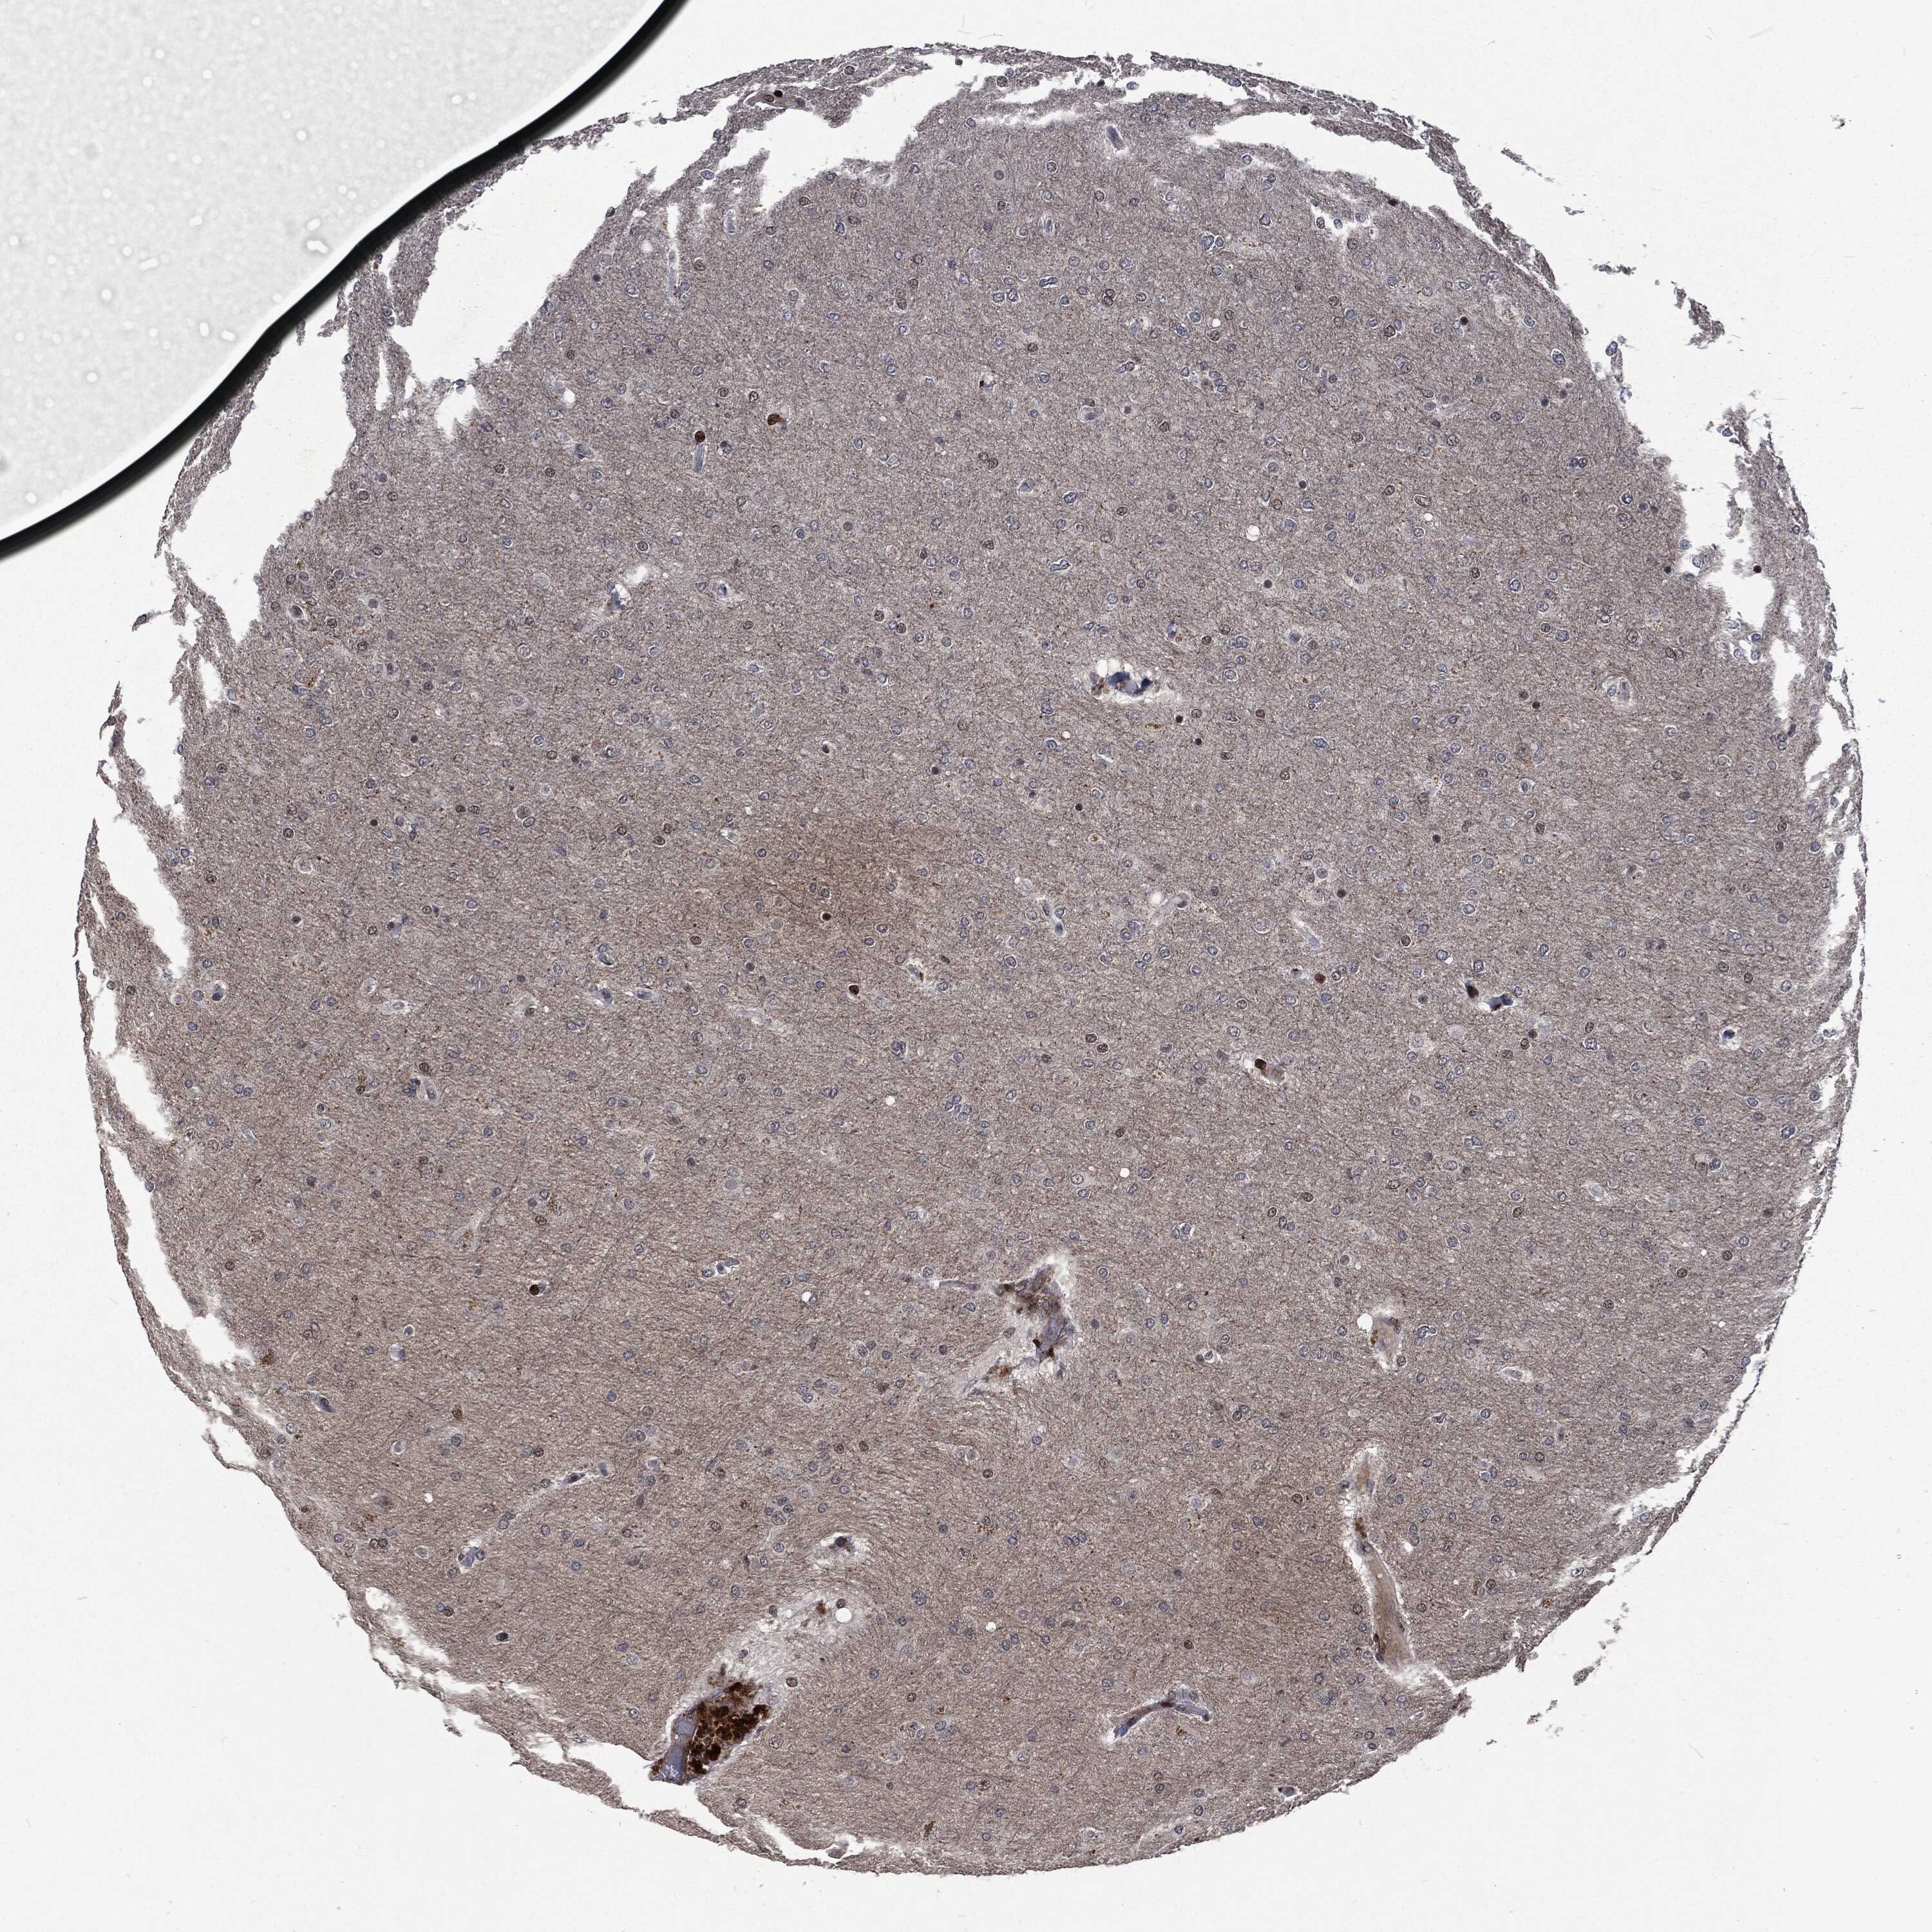

GLIOMA - Protein expressioni

A mouse-over function shows sample information and annotation data. Click on an image to view it in a full screen mode. Samples can be filtered based on level of antibody staining by selecting one or several of the following categories: high, medium, low and not detected. The assay and annotation is described here.

Note that samples used for immunohistochemistry by the Human Protein Atlas do not correspond to samples in the TCGA dataset.

Antibody stainingi

Antibody staining in the annotated cell types in the current human tissue is reported as not detected, low, medium, or high, based on conventional immunohistochemistry profiling in selected tissues. This score is based on the combination of the staining intensity and fraction of stained cells.

Each image is clickable and will lead to virtual microscopy that enables deeper exploration of all samples and also displays staining intensity scores, fraction scores and subcellular localization as well as patient and tissue information for each sample.

Glioma, malignant, High grade

Glioma, malignant, Low grade

Glioma, malignant, NOS